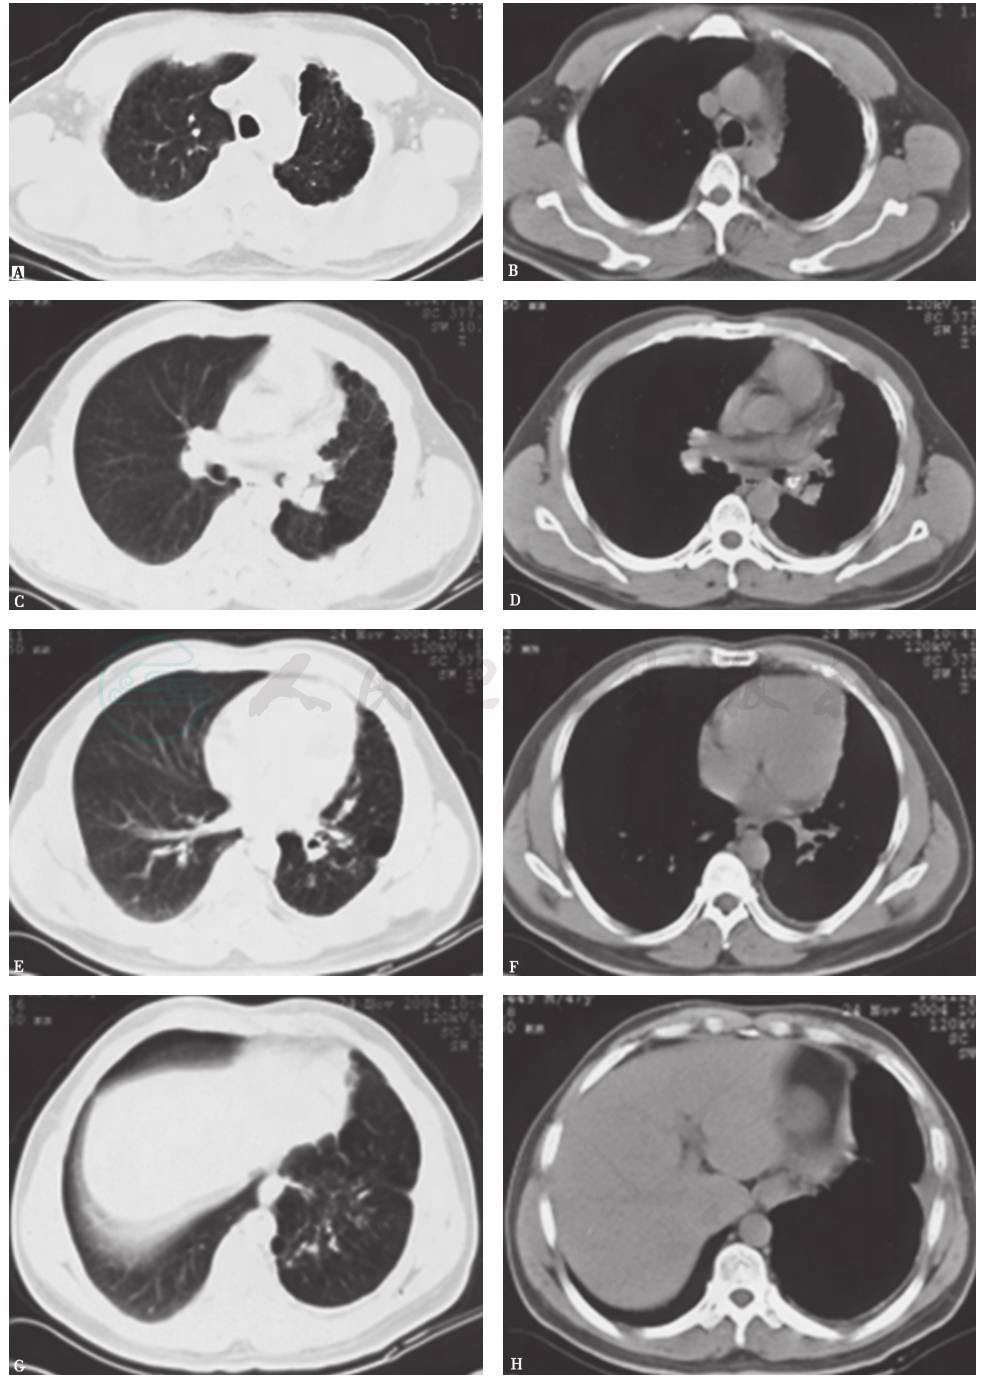

图9 2年半前胸部CT表现

胸部CT可见左主支气管被高密度钙化灶管腔几近完全阻塞,左上肺代偿性肺气肿和肺大疱进一步加重,左下肺体积略增大伴多发肺大疱,并见左下肺前内基底段实变;右肺代偿性含气较前有所减轻

图10 1年前胸部CT表现

胸部CT可见左主支气管病灶同前,左上肺代偿性肺气肿和肺大疱进一步加重,左下肺多发肺大疱增多,左下肺前内基底段实变仍存在;右肺代偿性含气未见加重